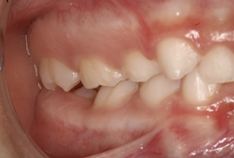

En el examen intraoral se observa mordida cruzada anterior. Las líneas medias dentales coinciden. Esto indica correcta alineación central. Tanto el arco superior como el inferior presentan forma en U, lo que sugiere un buen espacio para la dentición y una correcta disposición de los dientes en ambos arcos.

Figura 4. Mordida cruzada anterior Figura 5. Arco superior en forma de U

La relación molar tanto del lado derecho como del izquierdo se clasifica como Clase I, indicando una correcta intercuspidación molar y oclusión funcional bilateral. Esto sugiere un buen equilibrio dentoalveolar y favorece la estabilidad oclusal general.

Figura 7. Relación molar derecha Figura 8. Relación molar izquierda